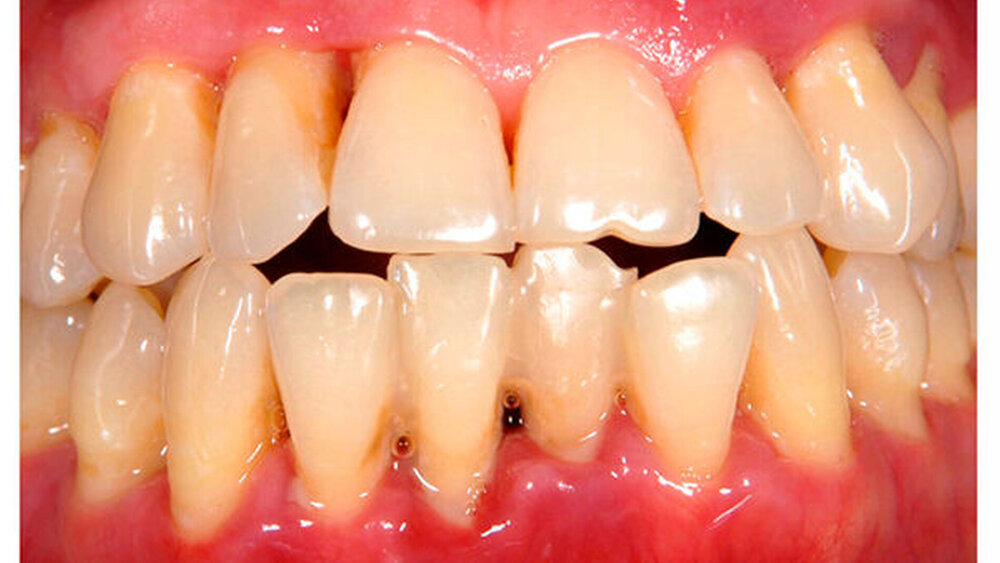

Bei etwa einem Viertel der Patienten lag bei Reevaluation ein Rezidiv vor. Als Risikofaktoren für das Auftreten eines Rezidivs konnten Rauchen, ein hoher mittlerer Gingival Bleeding Index (Ainamo & Bay 1975) und hohe nachweisbare Mengen der Parodontalpathogene T. forsythia und T. denticola festgehalten werden. Patienten, die regelmäßig zur UPT erschienen waren hingegen vor Rezidiven geschützt. Ebenso zeigte die Compliance zur UPT einen signifikant positiven Einfluss auf die Kariesinzidenz.

Um Zahnverlust und Rezidive zu vermeiden sowie das Auftreten einer Karies gering zu halten, sollten Patienten mit AgP regelmäßig an der UPT teilnehmen, wobei das UPT-Intervall anhand der vorgeschlagenen modifizierten PRA ohne Einschluss des IL-1ß-Polymorphismus festgelegt werden sollte.